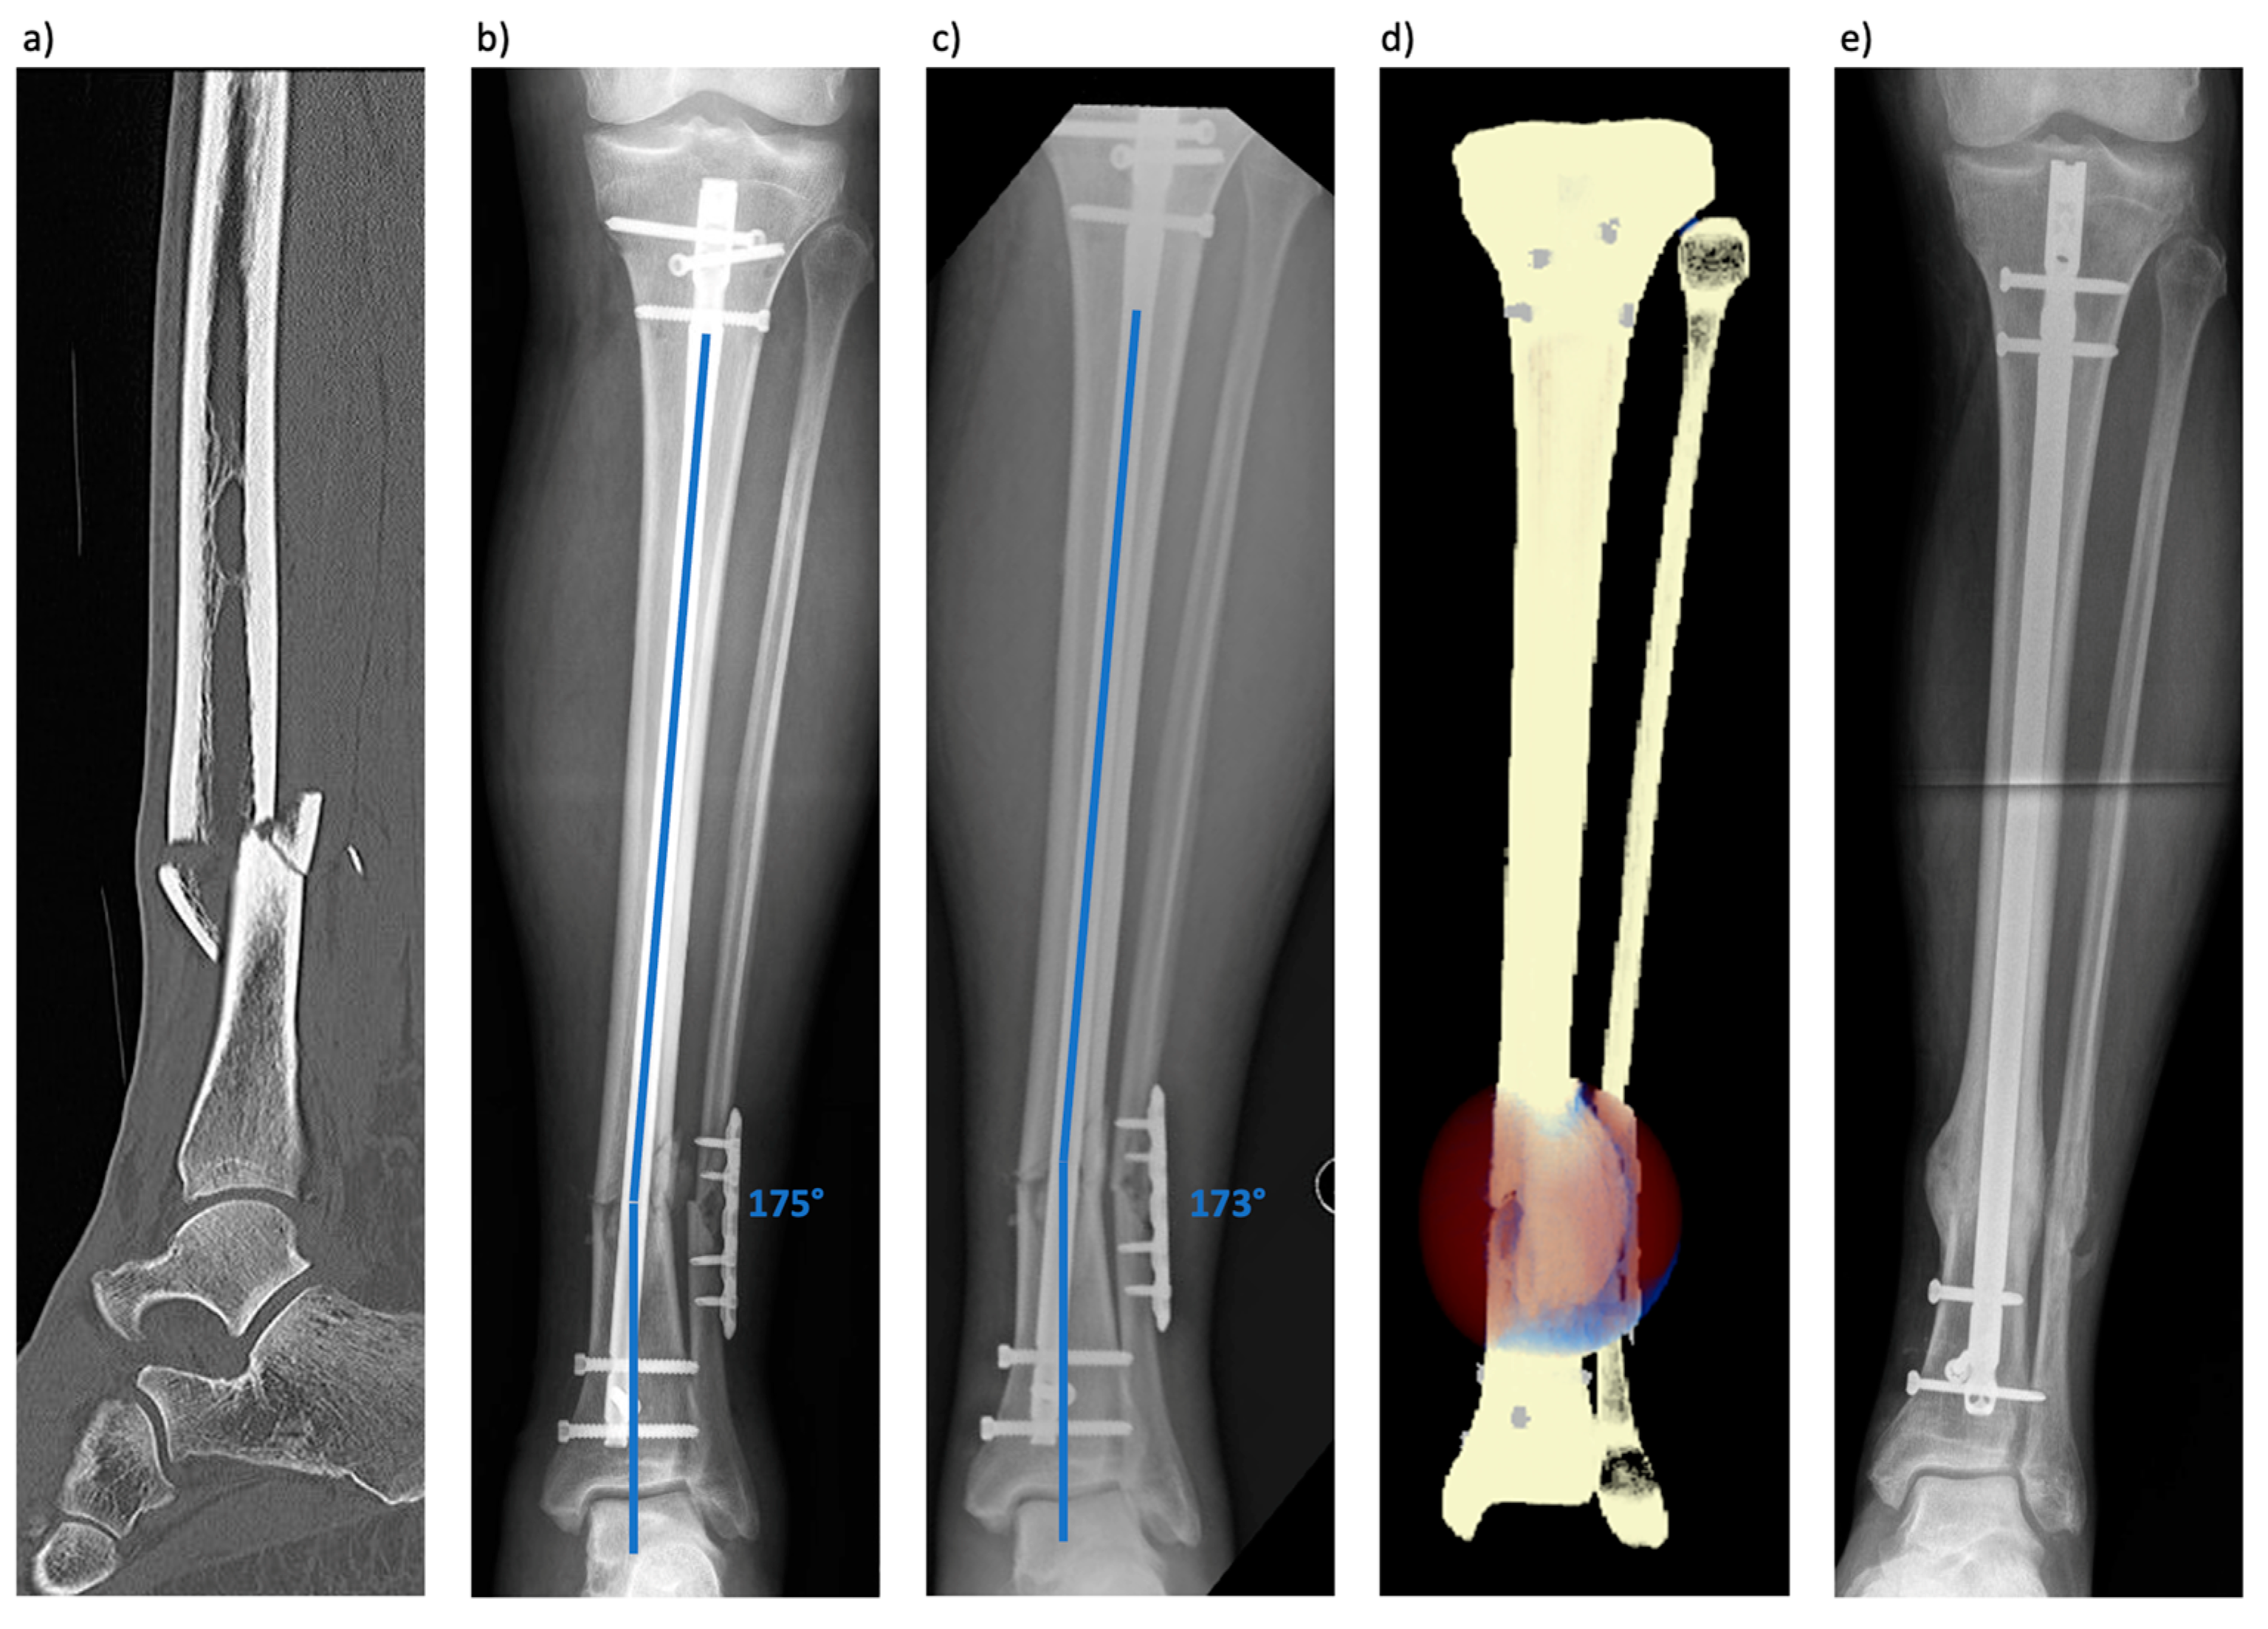

3.1. Patient 1 (Tibial Fracture)